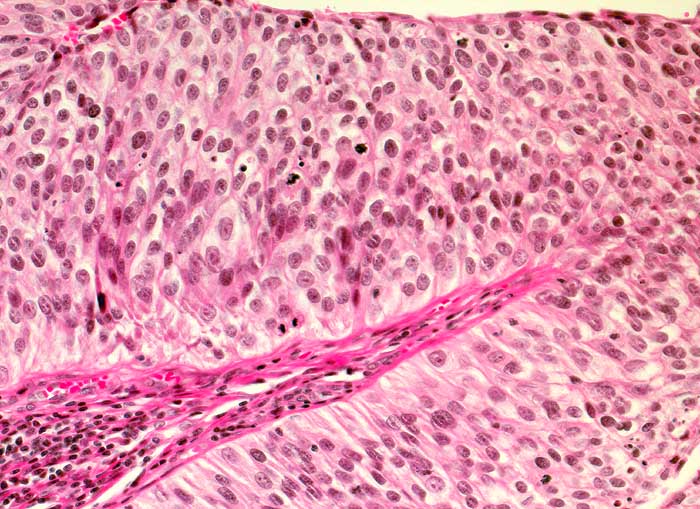

PathoPic – image database / PathoPic ID 6541 - Nicht invasives papilläres Urothelkarzinom, low grade pTa, G2

Nicht invasives papilläres Urothelkarzinom, low grade pTa, G2

Das bedeckende Urothel des papillären Tumors ist deutlich verdickt. Verglichen mit normalem Urothel sind die Zellen dieses mässig differenzierten Tumors leicht vergrössert, unregelmässig gelagert und hyperchromatisch. Gelegentlich sind Mitosen nachweisbar. Die Epithel-Stroma Grenze ist scharf.

Rezidivierende Urotheltumoren. Aktuell: Ureter-Tumor.

Histologie

200